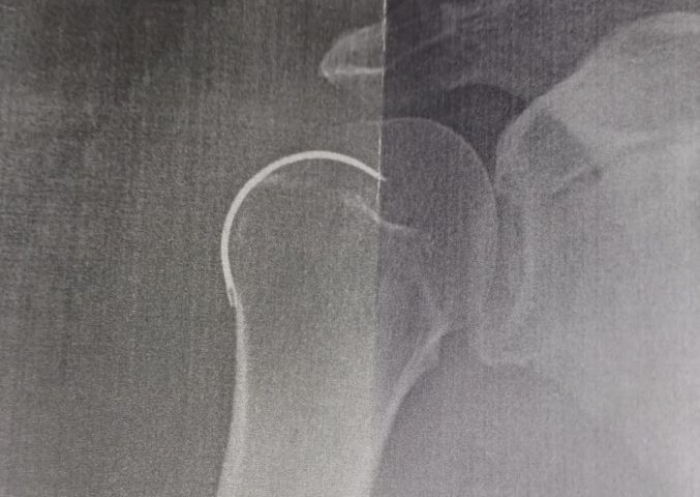

Uma agulha foi esquecida dentro de um paciente durante uma cirurgia no ombro direito, realizada no Hospital Santo Antônio, em Armazém.

O morador de Capivari de Baixo Josoel Geraldo Serafim, de 62 anos, passou pelo procedimento no dia 6 de outubro do ano passado e somente na última semana é que o item foi retirado. Segundo ele, o médico teria esquecido a agulha de sutura dentro do ombro.

Contudo, foi ao realizar um novo raio-X que os médicos descobriram a presença do objeto cirúrgico esquecido no paciente.